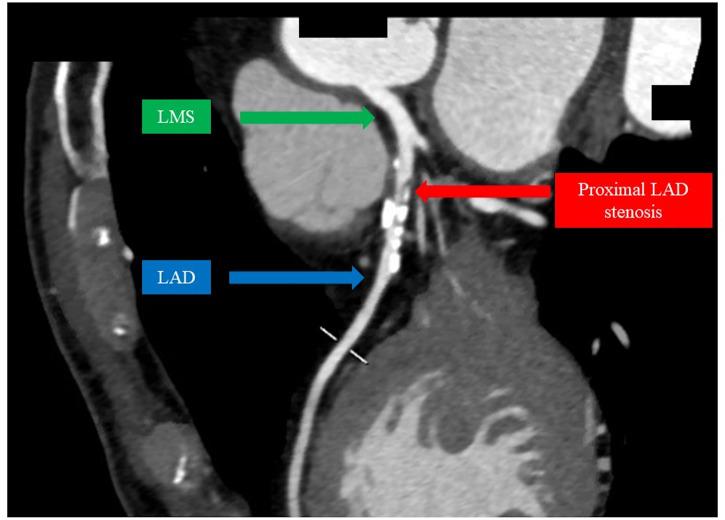

A 75-year-old gentleman presented with a history of progressive exertional presyncope. His investigations demonstrated normal cardiac structure, function, and rhythm. He underwent an exercise stress test, which demonstrated a significant reduction in peak blood pressure with equivocal electrocardiogram changes and absence of ischaemic symptoms. In view of his age and gender, a computerized tomography coronary angiogram (CTCA) was organized to exclude obstructive coronary artery disease (CAD). Intriguingly, the CTCA demonstrated a severe proximal left anterior descending (LAD) artery stenosis. This stenosis was confirmed to be functionally significant using invasive coronary physiology and was treated with percutaneous coronary intervention. At follow-up, there was no recurrence of exertional presyncope and the patient was continuing to return to his baseline function.

一名75岁男性有进行性运动性先兆晕厥病史。他的检查显示心脏结构、功能和节律正常。他接受了运动负荷试验,结果显示峰值血压显著降低,心电图改变不明确且无缺血症状。鉴于他的年龄和性别,安排了计算机断层扫描冠状动脉造影(CTCA)以排除阻塞性冠状动脉疾病(CAD)。有趣的是,CTCA显示左前降支(LAD)动脉近端严重狭窄。使用侵入性冠状动脉生理学方法证实该狭窄具有功能意义,并接受了经皮冠状动脉介入治疗。随访时,运动性先兆晕厥未复发,患者继续恢复到基线功能。